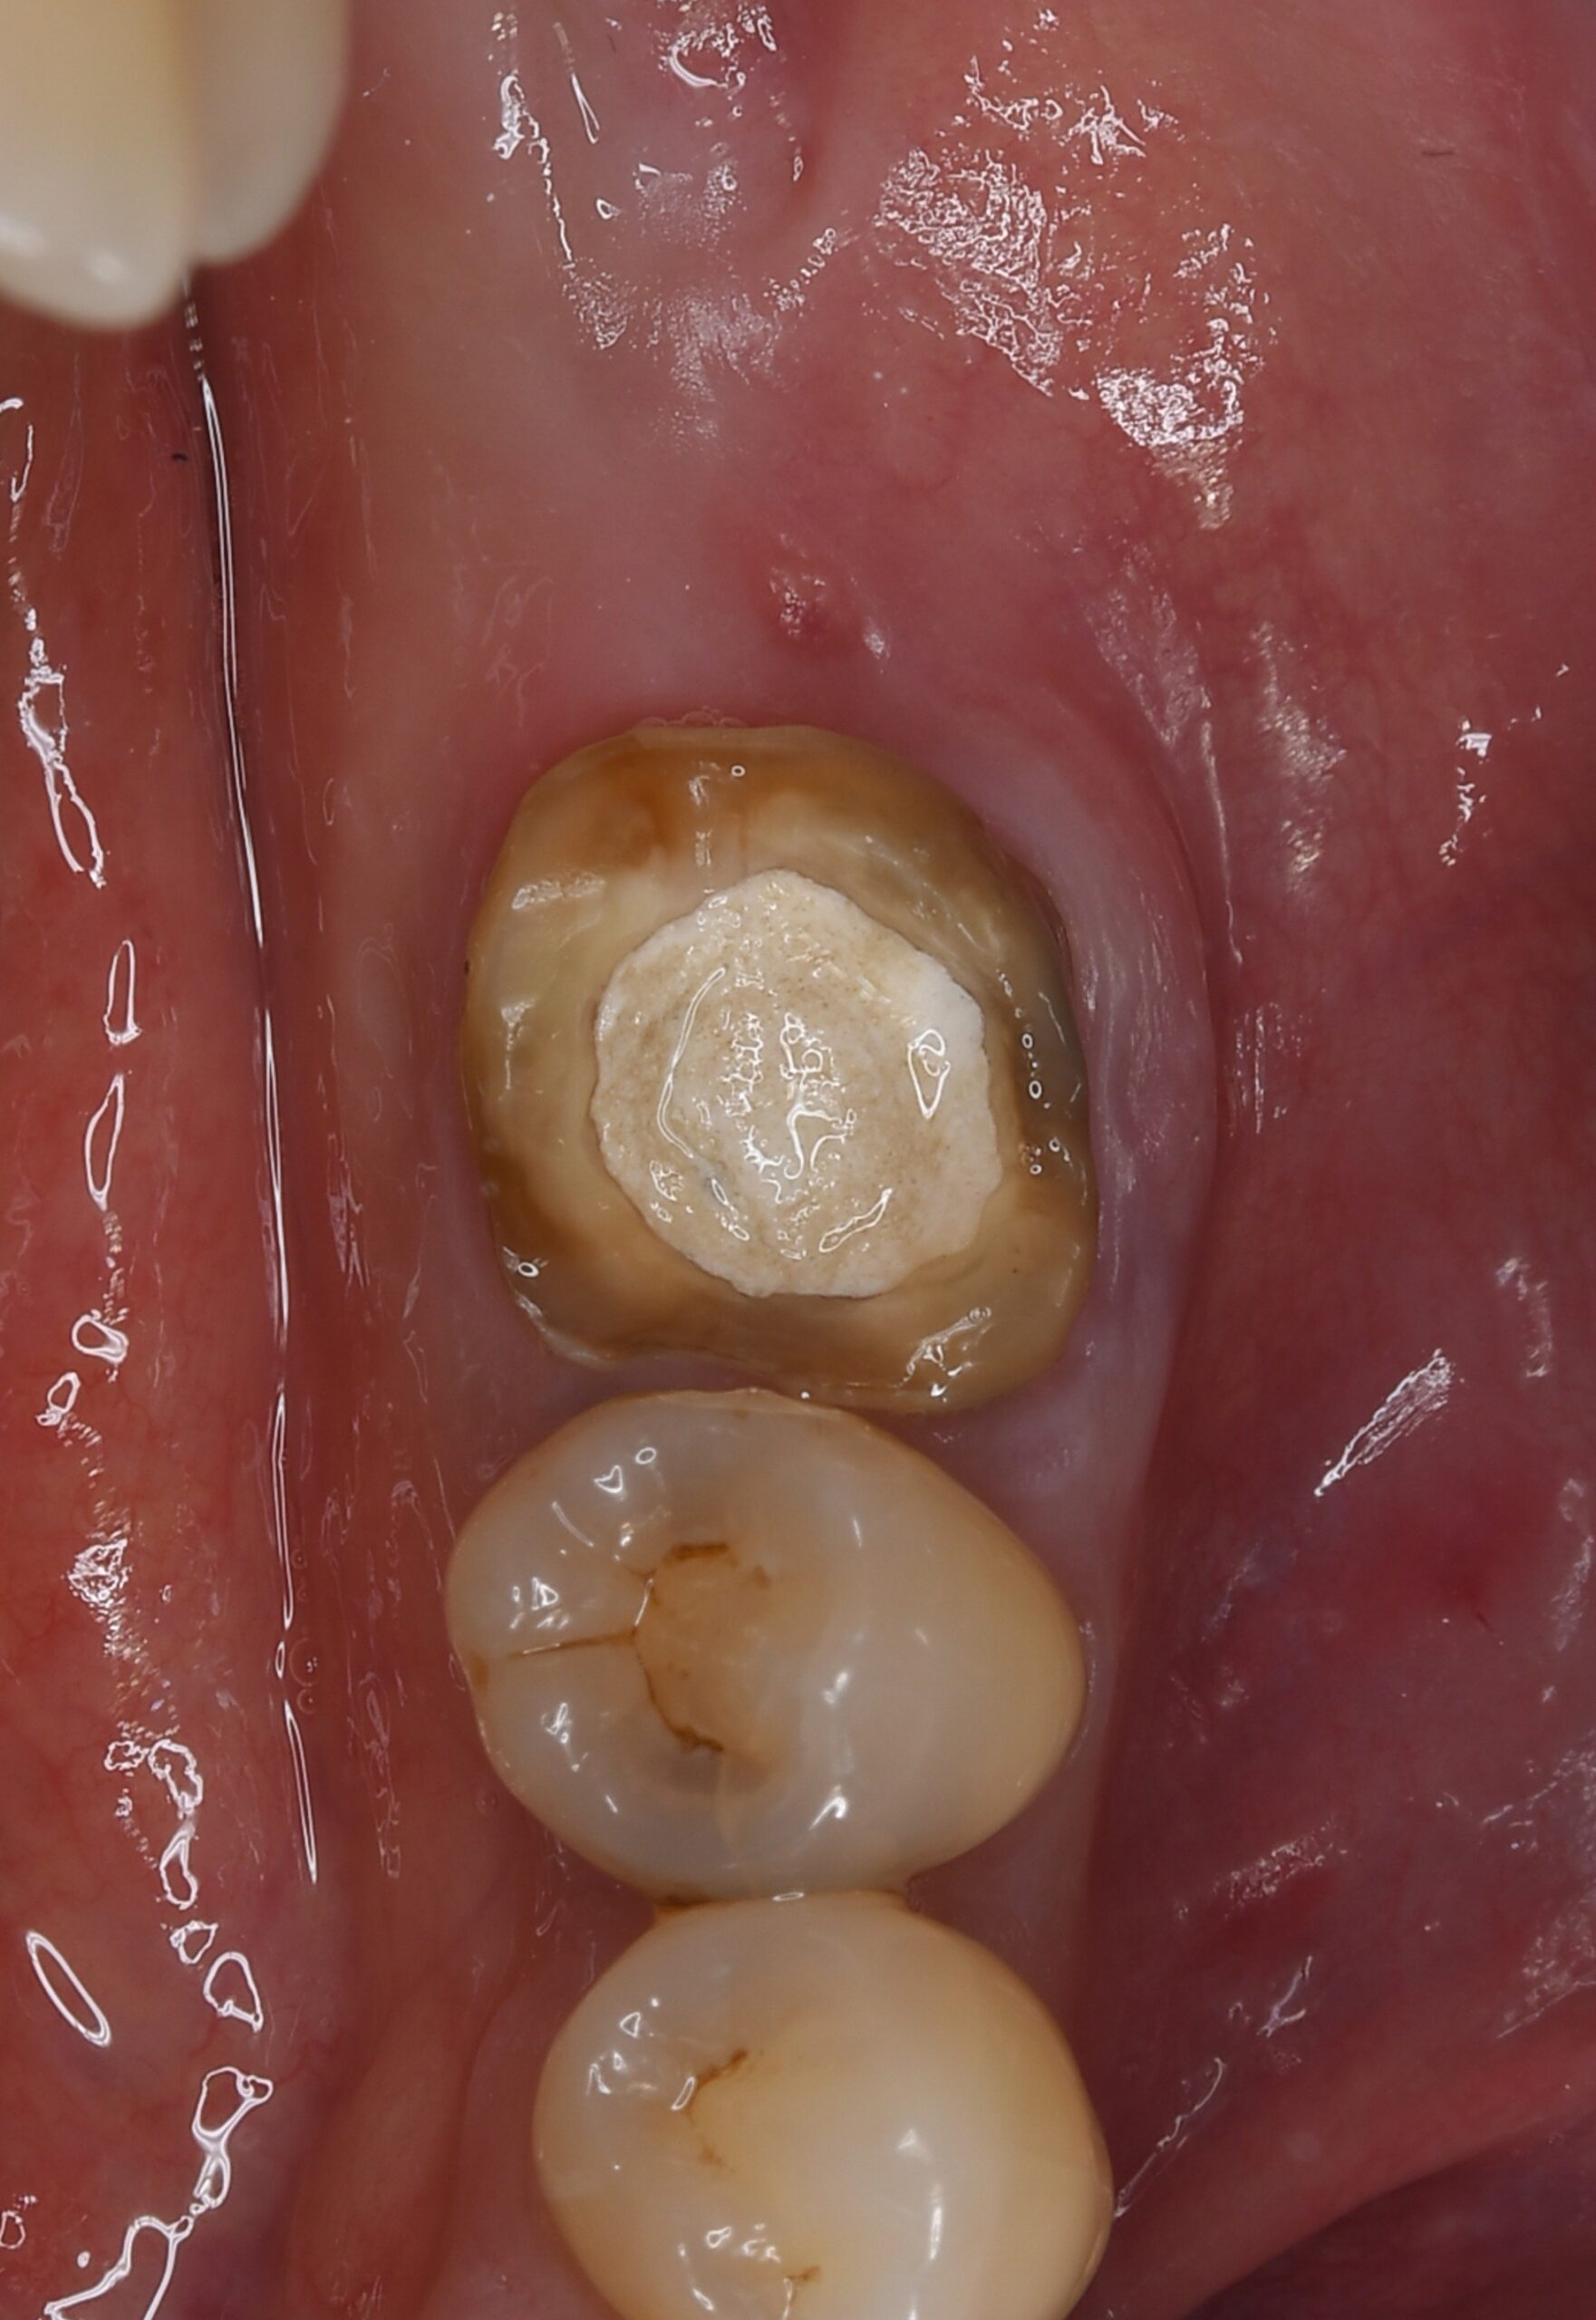

症例3

治療の流れ

親知らずの抜歯

| 患者様データ | 40代 女性 |

| 来院時の主訴 | 「左側奥歯で噛むと痛い。」 |

| 医院の診断 | 歯根破折、慢性根尖性歯周炎 |

| 治療費 | 総額:330,000円(税抜) 【内訳】 歯牙移植150,000円、ファイバーポストコア20,000円、ダイレクトボンディング80,000円×2 |

| リスクと副作用 | ①根管治療歯は長期的には破折するリスク ②長期的なメインテナンスが必要 ③歯根の外部吸収 |

抜歯が必要になった際に余っている親知らずがあれば移植歯として利用することができます。 術前に撮影したCT画像から3Dプリンターを用いて親知らずのレプリカを作製することで、親知らずが乾燥することを防ぎ、成功率が上がるよう努力しています。 |